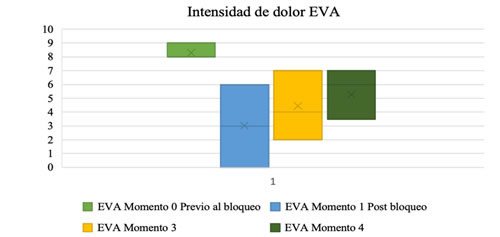

El 93 % (n = 35) de los pacientes llevados a bloqueo cluneal presentaron un EVA severo (mayor a 7) previo al procedimiento. El 28 % (n = 11) de los pacientes presentaron en el postbloqueo inmediato una disminución del dolor con un EVA menor de 6; en el primer control el 57 % (n = 22) conservaron la mejoría del dolor y el 10 % (n = 4) había retornado a su estado basal de dolor. Sin embargo, para el segundo control el 10 % (n = 4) de los pacientes no presentaron cambios en la intensidad del dolor de acuerdo con la valoración realizada previamente al procedimiento y el 78,9 % (n = 30) conservaba mejoría en la intensidad del dolor comparado con la EVA aplicada previo a bloqueo (Figura 3).

*EVA: Escala visual análoga del dolor: de 0 a 10.

Fig. 3. Diagrama de caja y bigotes de la intensidad del dolor en cada momento. Momento 0: Previo a bloqueo el 93 % de los pacientes llevados a bloqueo cluneal presentaron un EVA severo (mayor a 7). Momento 1: inmediato al bloqueo, el 28 % de los pacientes presentaron una supresión del dolor con un EVA menor a 6. Momento 2 (primer control con media de 81 días [± 67]) el 57 % conservaron la mejoría del dolor, para el Momento 3 (segundo control post-intervención con media de 267 días (± 135,5) el 78,9 % conservaba mejoría en la intensidad del dolor.

El tiempo de realización de primer, segundo y tercer momento está comprendido entre 81 (± 67) y 267 días (± 135,5); después del bloqueo la intensidad del dolor en el primer momento fue 3, segundo momento 4, y tercer momento 6 (Tabla IV) evaluados con test de Wilcoxon con un valor (p < 0,001).